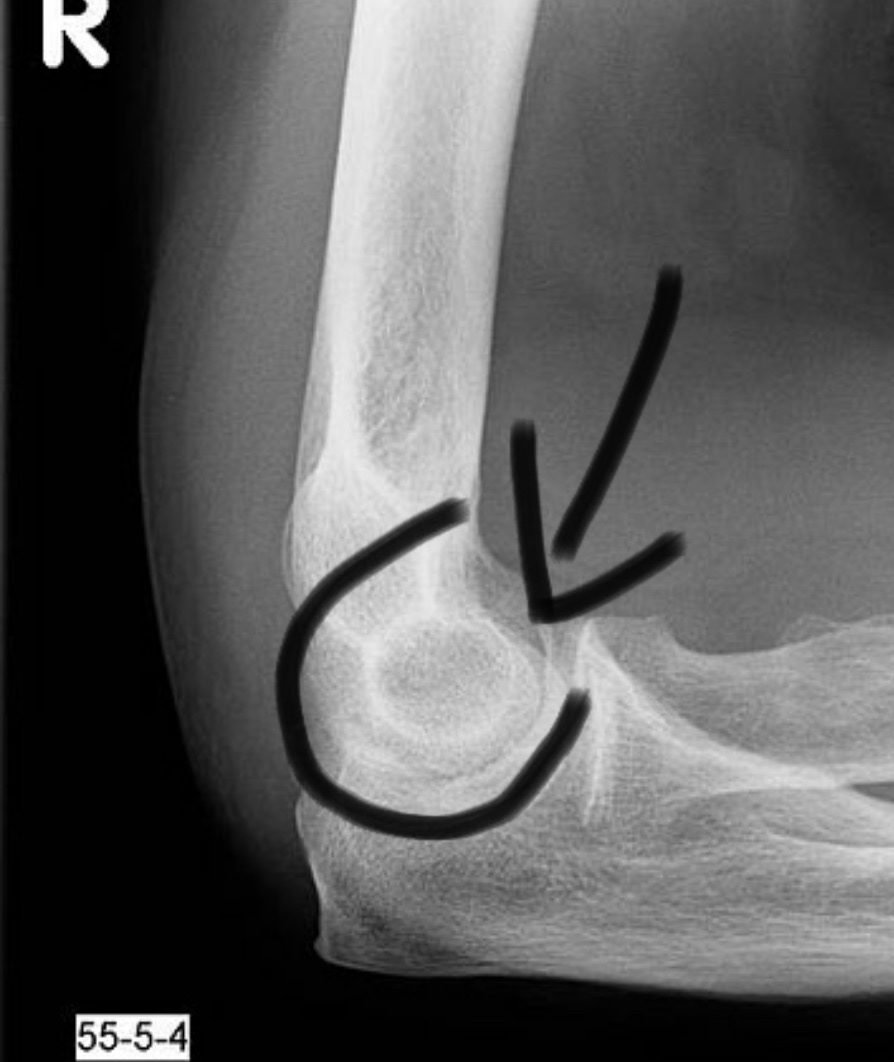

Ellenbogen gebrochen wie lange gips. Die offene Gipsschiene wird durch einen geschlossenen Gipsverband ersetzt. 4 Wochen warscheinlich mindestens. Hierfür wird der Arm in einem Gips ruhiggestellt sodass die beiden Frakturenden wieder zusammenwachsen können.

Für zwei Wochen war ein Gips dran. Normalerweise ist eine Röntgenkontrolle vor der Gipsabnahme Routine. Weigl Die Genesungszeit ist stark von individuellen Umständen abhängig.

In der Regel reicht allerdings bereits eine 1-2 wöchige Ruhigstellung aus bei komplexen Brüchen auch 3-4 Wochen um den Bruch so zu stabilisieren das eine Mobilisation des Gelenkes möglich ist. Am Tag nach der Operation erfolgt eine nochmalige Röntgenkontrolle. Wie lange der Gips getragen werden muss ist in erster Linie von der Schwere der Verletzung abhängig.

6 Wochen eine abschließende Untersuchung statt dann ist die Fraktur in der Regel gut ausgeheilt. Hatte recht lange Schmerzen und auch extrem geschwollenen Arm.